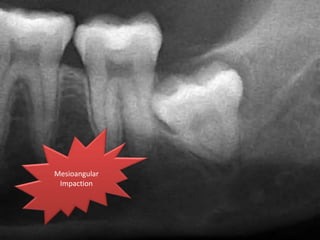

Angulation of impaction

Based on Winter's classification, the angle between the

longitudinal axis of the second and third molars

Mesioangular

impaction